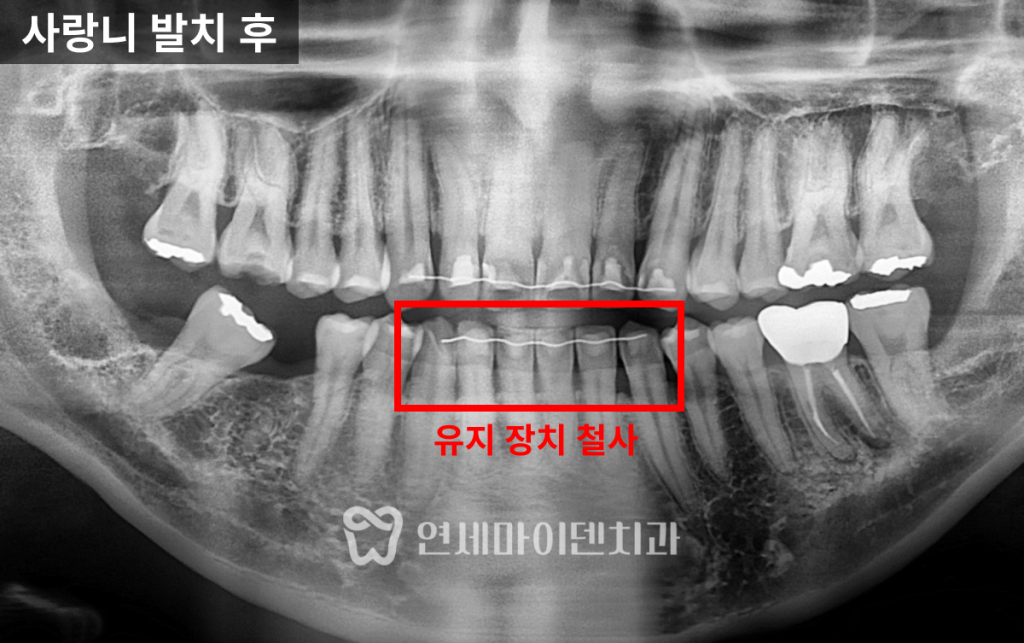

장기적으로는 불리할 가능성이 큽니다.사랑니 발치가 먼저 필요했던 이유

이 케이스에서는 위아래 사랑니가 모두 존재했고

특히 아래 사랑니는

쓰러진 7번 어금니를 세우는 과정에서

물리적으로 이동을 방해하는 위치였습니다.또한 기능적으로도 큰 역할을 하지 않는 상태였기에

사랑니는 모두 발치하는 방향으로

치료 계획을 세웠습니다.교정과 임플란트는

공간 싸움이라고 해도 과언이 아닙니다.불필요한 치아는 정리하고

목표 공간을 확보하는 것이 우선입니다.부분교정이 필요한 이유

부분교정으로 접근했습니다.부분교정의 핵심: 고정원 설계

이 환자분은 과거 교정 이력이 있어

앞니 안쪽에 유지장치가 남아 있었고,

이 장치가 고정원 역할을 해주었습니다.여기에 미니스크류를 추가해